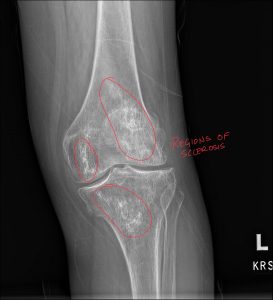

We are committed to enhancing patient care by delivering top-tier medical imaging evaluations and reports consistently. Our team of board-certified radiologists brings specialized expertise in diagnostic imaging, with a particular focus on chiropractic radiology that specializes in spine and musculoskeletal imaging. We strive to provide not just readings, but invaluable consultations, ensuring each patient receives the best that modern radiology has to offer. Our dedication to accuracy, speed, and reliability in off-site image interpretations sets us apart as trusted partners in healthcare.